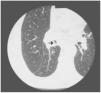

His general condition was good, but he had reduced lung sounds in the lower third of the right hemithorax. The PaO2 in room air was 73mmHg. Chest X-ray showed an opacity in the lower right hemithorax, and CT scan revealed an endobronchial mass causing obstruction of the lumen of the inferior lobar bronchus (Fig. 1), with an irregular, approximately 3cm, extension into the lung parenchyma. Sputum cytology showed malignant cells and the histology of the endoscopic bronchial biopsy revealed a malignant tumor with sarcomatous features. There was no evidence of tumor elsewhere on abdominal and brain CT scans and bone scintigraphy. The endobronchial tumor mass was subsequently removed with laser, and histological examination showed a spindle cell tumor with marked nuclear pleomorphism, multinucleated tumor giant cells and numerous mitotic figures (Fig. 2). There was no evidence of epithelial differentiation. The tumor was immunoreactive for vimentin and focally for CD68, and negative for multiple high and low mol. wt. cytokeratins, epithelial specific antigen, epithelial membrane antigen, actin, smooth muscle actin, desmin, S-100 protein and CD34. CD117 immunostaining showed no mast cells within the tumor. The cell proliferation index with Ki 67 was 60 %. A diagnosis of pleomorphic undifferentiated sarcoma was made.